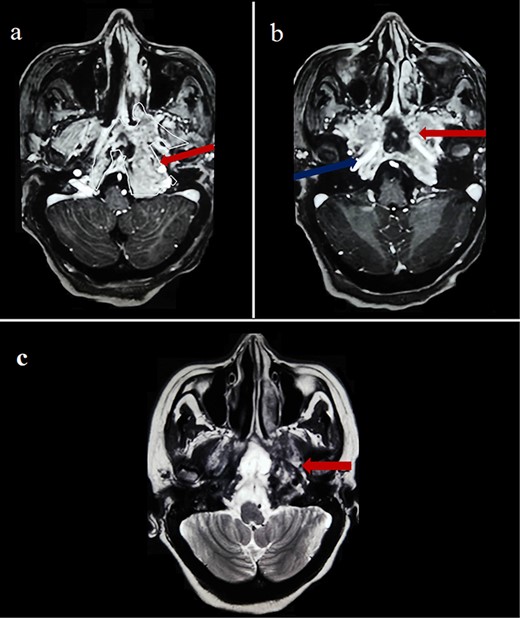

Cerebral computed tomography (CT) revealed a 65-mm hyperdense tumor invading the sphenoid bone and sinus, and eroding the adjacent skull base and clivus. On magnetic resonance imaging (MRI), the tumor appeared isointense on T1 and hypointense on T2-weighted images, showing mild heterogeneous enhancement after gadolinium injection. Local compression and extension to the left cavernous sinus, internal carotid artery, and optic chiasm were observed (Fig. 1).

Cerebral MRI (axial views) showing a 65-mm lesion centered on the sphenoid bone (red arrow) with extension to the internal carotid artery (blue arrow), demonstrating iso-intensity with mild heterogeneous enhancement on T1-weighted (a, b) and hypo-intensity on T2-weighted (c).